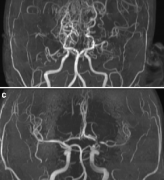

烟雾病是什么病?烟雾病的影像学诊断标准是什么?

Moyamoya称为基底神经节的区域的大脑底部动脉阻塞引起,疾病是指大脑某些动脉收缩的疾病。收缩和血块(血栓形成)会阻塞血流...